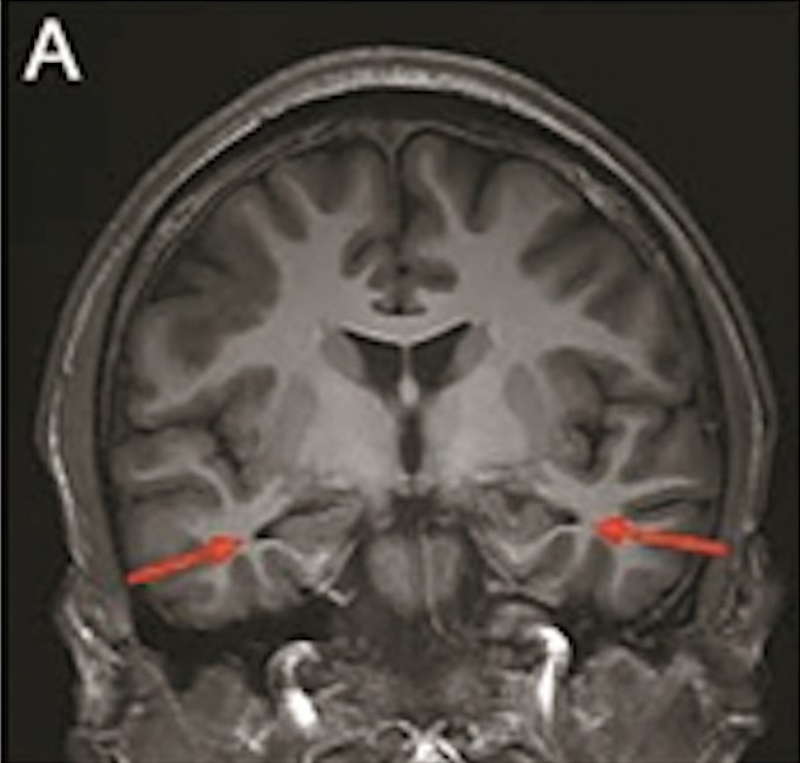

最年輕的19歲阿茲海默癥男子腦部掃描結(jié)果:

▲19歲阿茲海默癥(認知障礙癥/腦退化癥)男子腦部掃描結(jié)果。北京青年報

該名19歲男子到醫(yī)院接受多項檢查,包括腦脊液指標檢測及正電子掃描。結(jié)果顯示,他出現(xiàn)輕度腦萎縮等癥狀,最終被臨床診斷為“阿茲海默癥”。